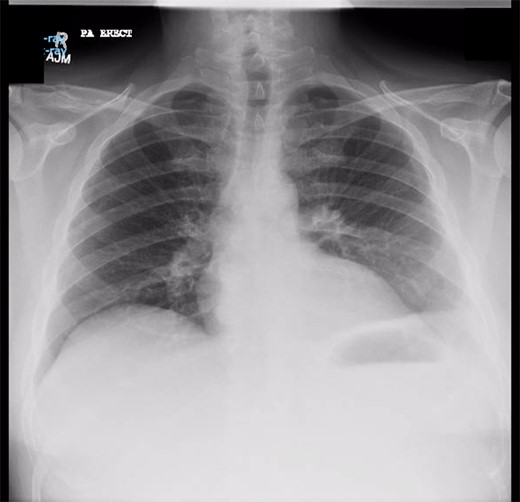

Chest X-ray in ICU following drainage showed what was thought to be Pneumomediastinum (Figs 1 and 2), and given this concern he was referred to the Cardiothoracic service. Subsequent CT suggested a large loculated hydro-pneumothorax, which in retrospect represented the drained Pseudocyst communicating through the diaphragm (Figs 3 and 4).

Chest X-ray post-transgastric drainage. Area of residual space highlighted with arrows.